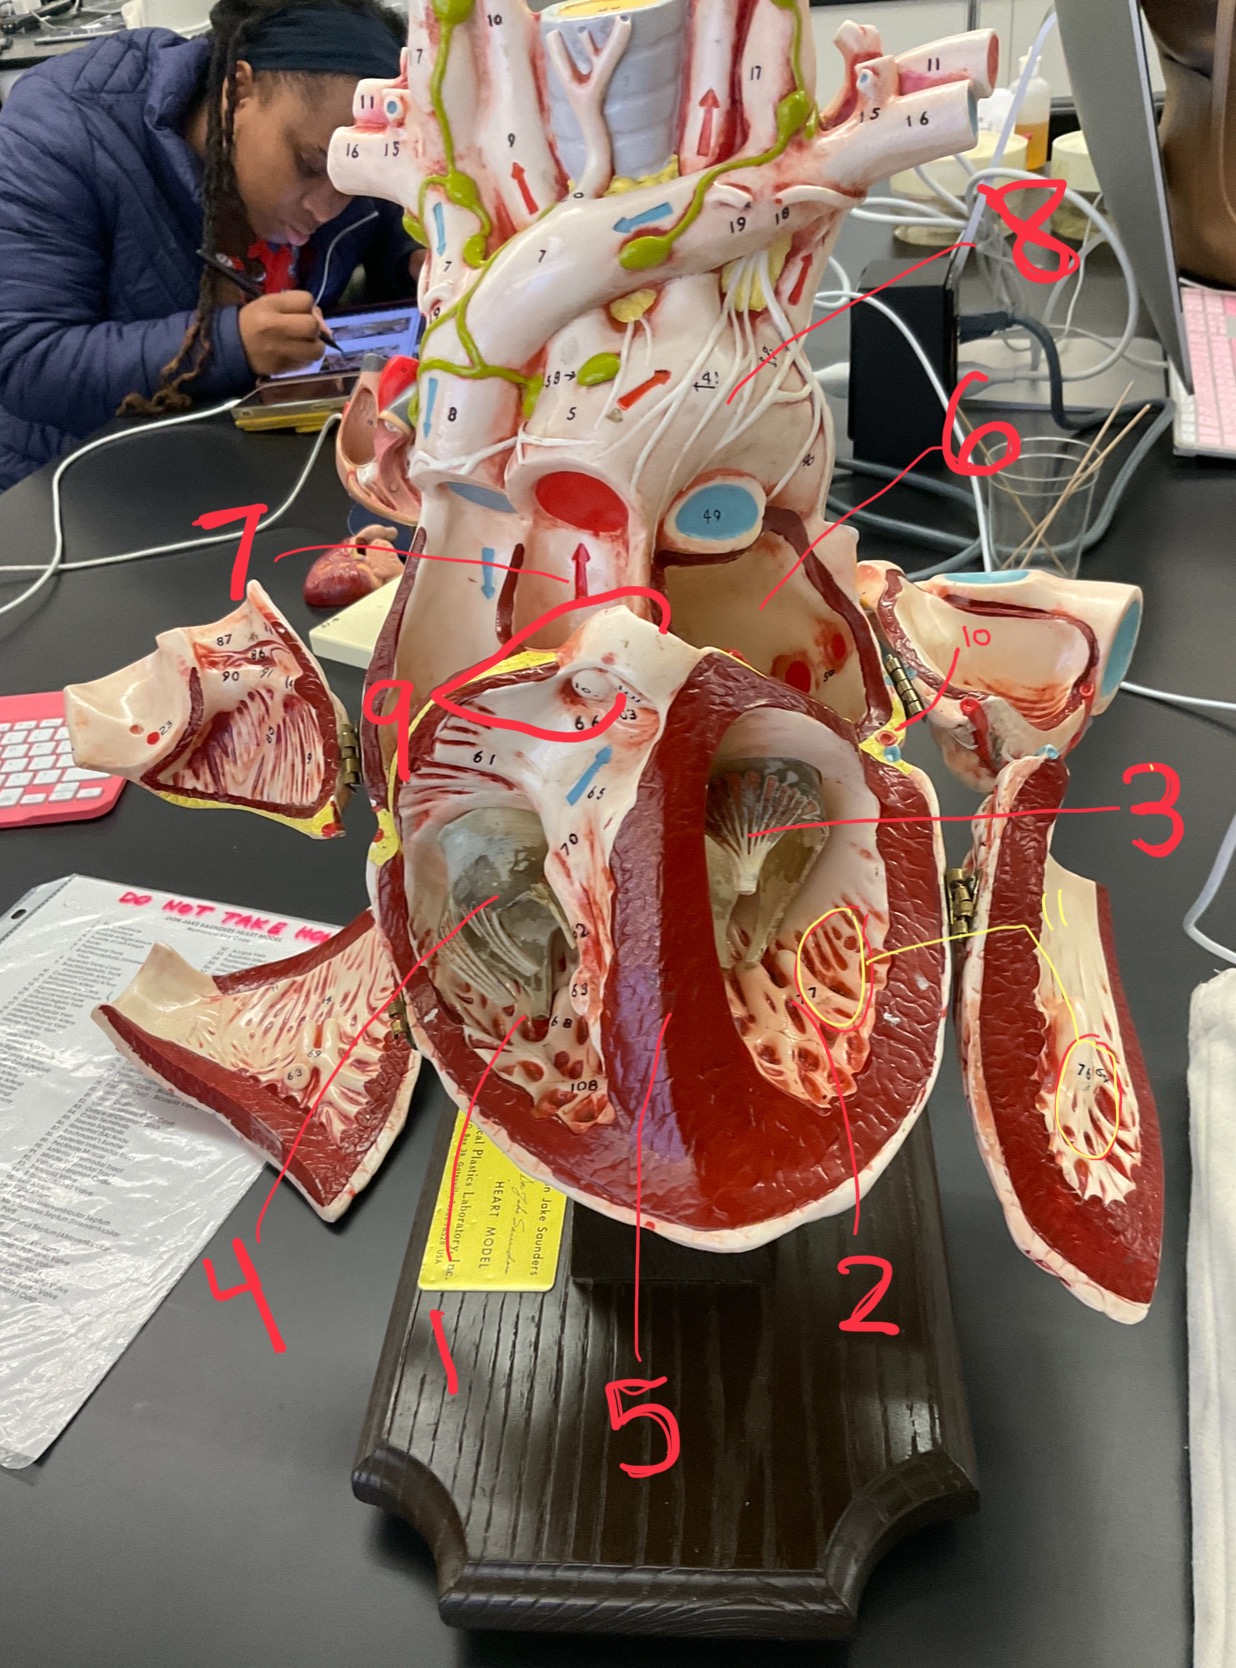

1

epicardium

2

3

endocardium

3

2

myocardium

4

1

coronary sinus

5

2

inferior vena cava

6

3

superior vena cava

7

1

right ventricle

8

2

left ventricle

9

3

bicuspid

10

4

tricuspid

11

5

interventricullar septum

12

6

left atrium

13

7

aorta

14

8

aortic trunk

15

9

pulmonary semi-lunar valve

16

10

atrevoventricullar sulus

17

11 (not smooth part)

trubeculae carneae

18

1

papillary muscle

19

2

chordae tendineae

20

4

pulmonary trunk

21

6

aortic trunk

22

aortic semi lunar valve

New cards

anterior inter ventricular sulcus